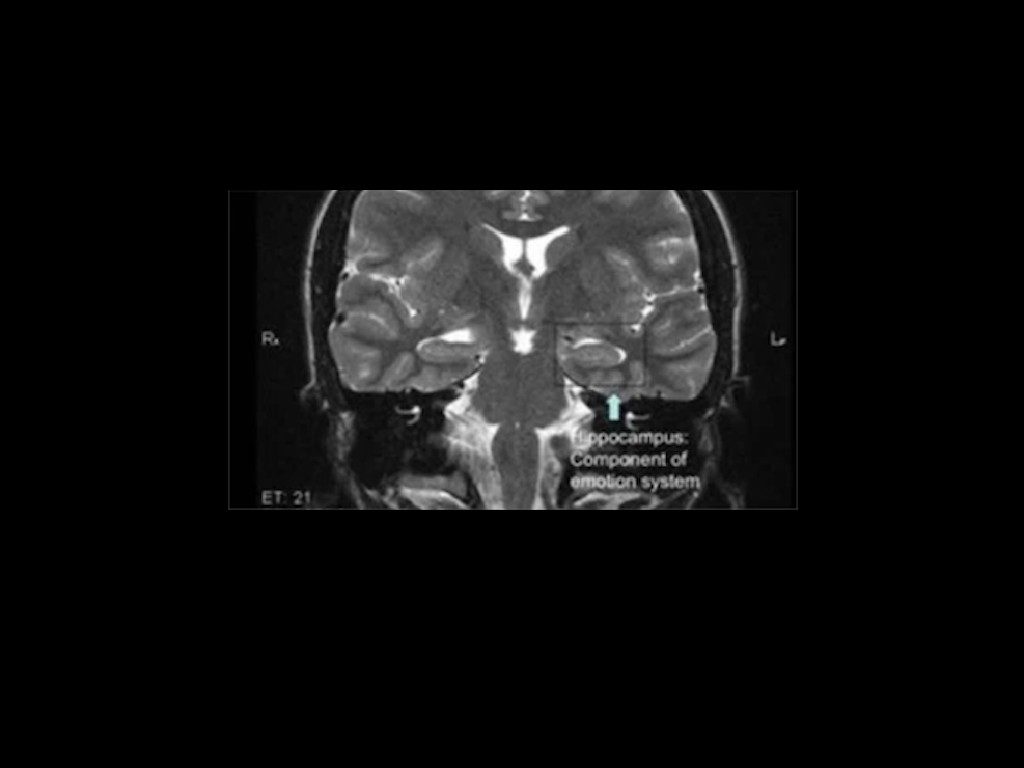

Dr. Najjar asked Cahalan to perform one simple task that would affirm all his suspicions about her condition. He had a theory about what the 24-year-old was really suffering from and needed this one test to confirm it.